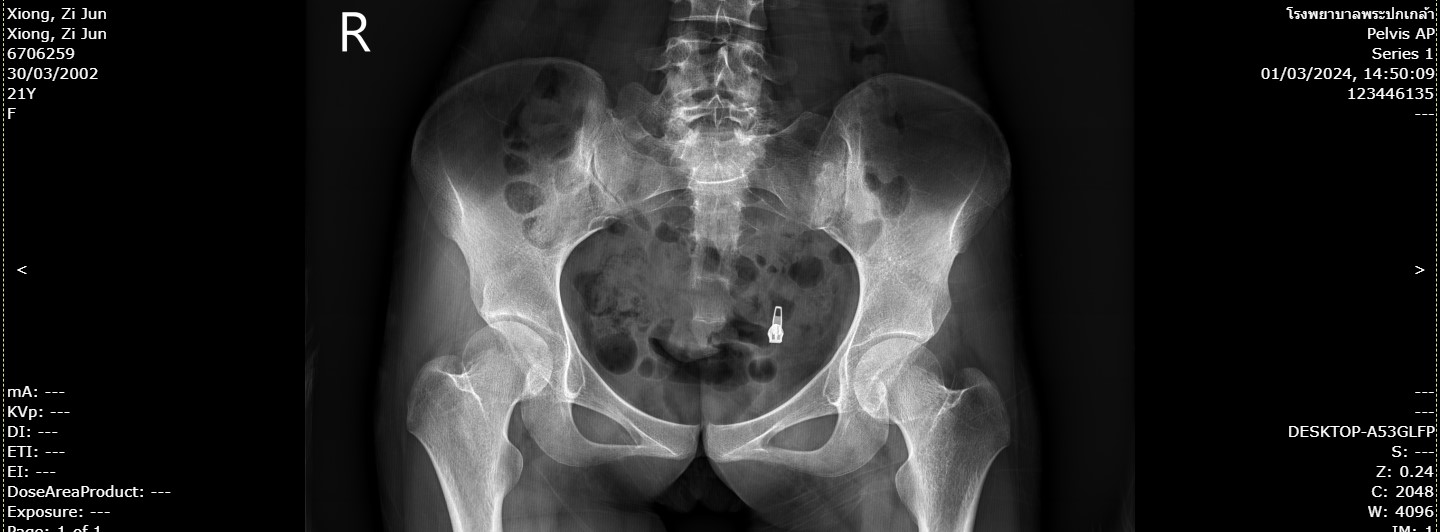

250xiong.jpg                                       19-Apr-2024 07:55              116521